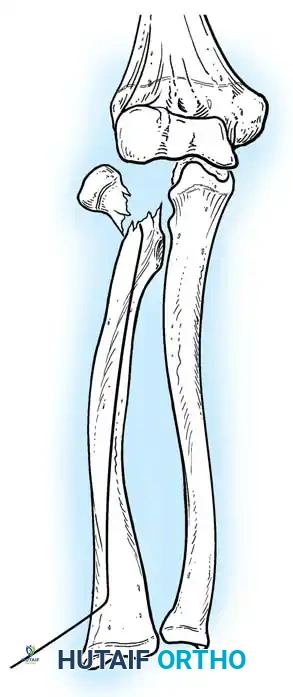

Fig. 33-39 A, Fracture occurring when elbow dislocation is reduced. B, Fractures occurring at time of elbow dislocation.

Fractures can present as angulated, translocated (shifted), or totally displaced. In the context of an elbow dislocation, the proximal fragment may become loose within the joint space or trapped, acting as a mechanical block to reduction.